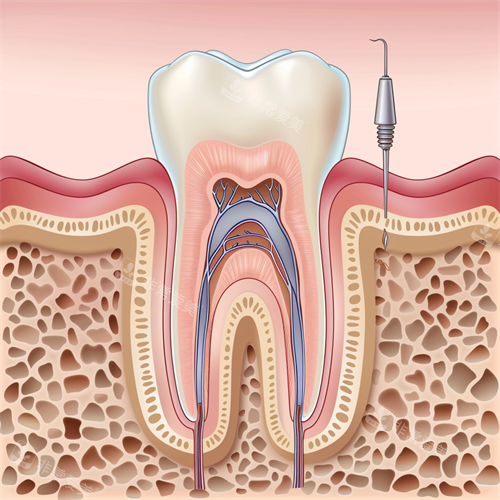

无论是常见的牙齿美白、补牙、拔牙,还是复杂的正畸、种植牙手术,医生们都能熟练操作,为患者提供个性化的治疗方案。